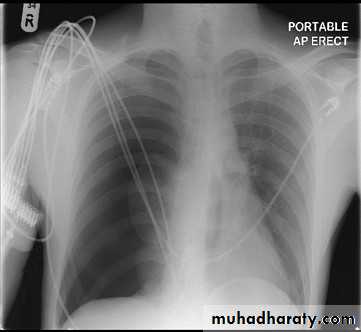

There are absent lung markings with a hyperlucent right hemithorax. The visceral pleura can be visualised as a curvilinear line that parallels the chest wall, separating the partially collapsed lung centrally from pleural air peripherally. An expiratory chest x ray aids in the detection of a small pneumothorax by decreasing the volume of aerated lung relative to the pneumothorax.